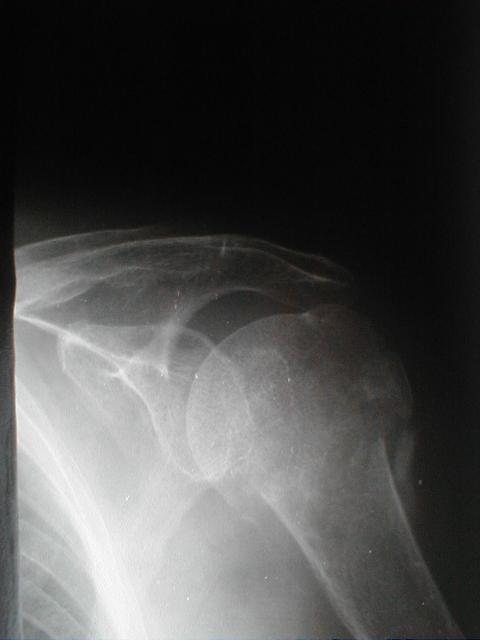

症例1

上腕骨頚部(外科)骨折と肩関節脱臼の合併症例

左上腕骨頚部(外転)骨折

左肩関節脱臼

自発痛著明、三角筋の膨隆消失、起居動作困難